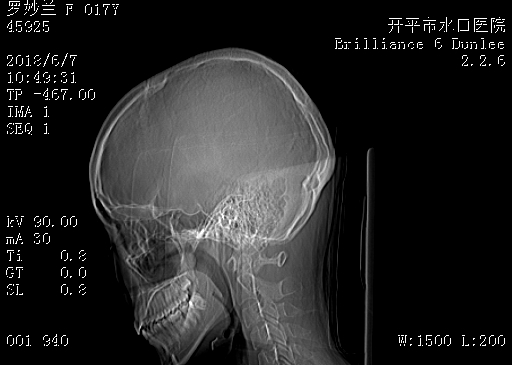

CT53290:女,17岁,反复头痛年余,请会诊,多谢!

女,17岁,反复头痛年余,请会诊,多谢!

未见异常,枕部低密度应该是蛛网膜颗粒。

颅脑CT平扫未见明显异常

第8层面,右侧枕部密度不均匀。

部分层面似见两侧枕叶密度稍欠均。必要时MRI检查。

颅脑CT平扫未见明显异常。

颅脑CT轴位平扫颅内未见明确异常。